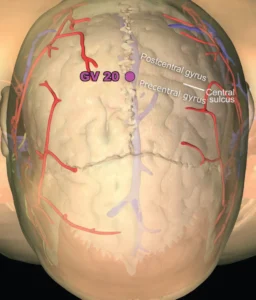

Meridian Zarządzający DU20 "Baihui"

- Rzut oka na lokalizację anatomiczną GV20 i kilku pozostałych punktów wzdłuż meridianu GV (kolorowe ryc. człowiek, MRI proj.strzałkowa: pies)

- Okolica GV20 jest unerwiana przez nerw czaszkowy V (nerw trójdzielny oraz nerwy z odcinka szyjnego C2 i C3 (m. in. nerw potyliczny mniejszy i większy)

Obszar meridianu GV jest też obszarem o bogatym unaczynieniu, sąsiaduje z przednią zatoką strzałkową, która drenuje boczne powierzchnie przednich półkul mózgowych. Tu w największej ilości uchodzą ziarnistości pajęczynówkowe w których zachodzi proces wchłaniania płynu mózgowo-rdzeniowego z przestrzeni podpajęczynówkowej do systemu krwionośnego.

Fizjologicznie proces ten chroni przed narastaniem nadmiernego ciśnienia wewnątrzczaszkowego.